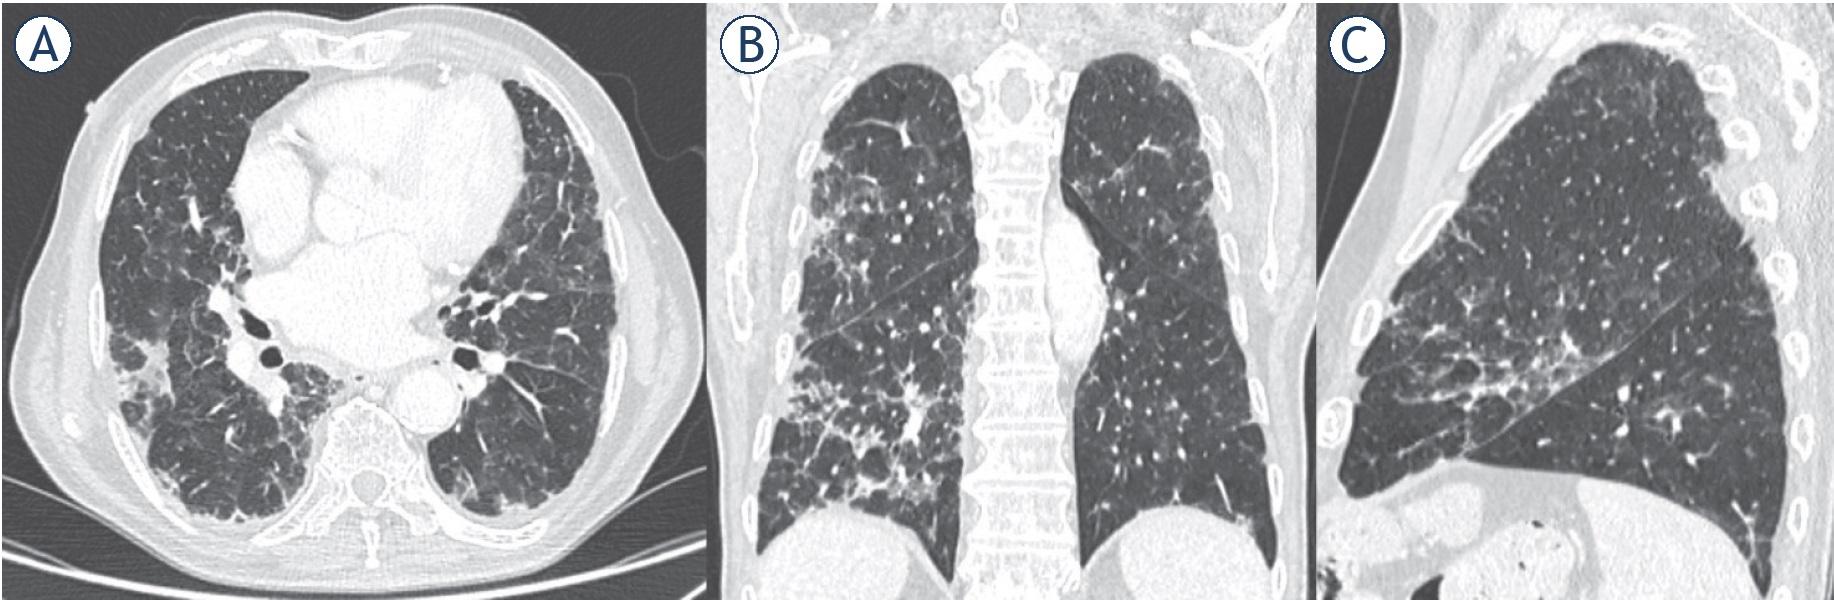

Dissipation stage. Two and 3weeks after the onset of clinical symptoms. “CT shows patchy consolidation or strip-like opacity. As time goes on, it showed grid-like thickening of interlobular septa, thickening and strip-like twist of bronchial walls and a few scattered patchy consolidations”7 (Figure 5).

Man, 76 year. CT shows strip-like opacity, grid-like thickening of interlobular septa, thickening and strip-like twist of bronchial walls and patchy consolidations. (A) Axial plane; (B) multiplanar reconstruction in coronal plane; (C) multiplanar reconstruction in sagittal plane.